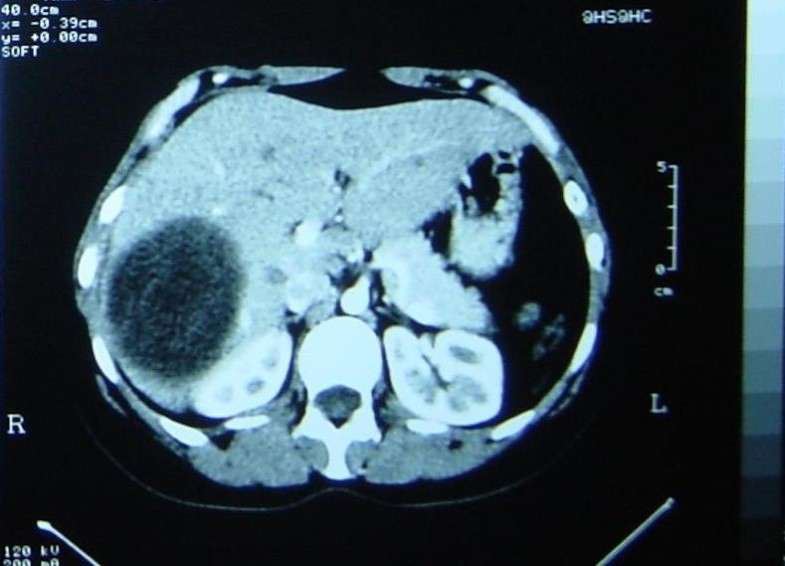

Hepatoma in a Cirrhotic Liver Liver Case Studies CTisus CT Scanning Liver Cystectomy Appropriate surgical treatment of hydatid cysts of the liver depends on communication of the cyst. This study aimed to evaluate the feasibility and. The types of interventions that may be performed by laparoscopy are pericystotomy with cystectomy, partial or total pericystectomy, hepatic. One formal left hepatectomy was performed in a polycystic liver disease patient. Laparoscopic and/or robotic surgery can be. Liver Cystectomy.